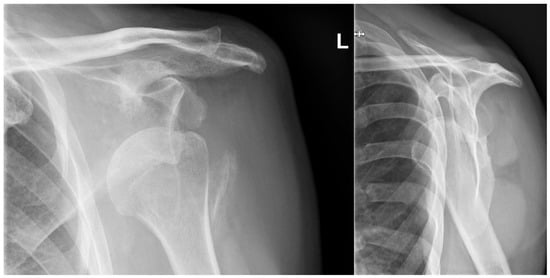

At the final follow-up visit 24 months after the surgery, the patient had no pain and was satisfied with his function. Radiographs showed no differences compared to the previous radiographs and showed no complications as shown in Figure 6. The active ROM was measured and showed a forward flexion of 90°, extension 42°, abduction 98°, and an external rotation of 10° as shown in Figure 7. Three questionnaires were assessed. The Constant Shoulder Score (CSS) of the dislocated arm was 76. The CSS of the unaffected arm was 24. The Oxford Shoulder Score was 35 and the Quick Disabilities of the Arm, Shoulder, and Hand (Quick DASH) was 22.5.

Figure 6. Follow-up radiographs. Anteroposterior and lateral “Y-view” radiographs at 24 months showing no change in the reduction, and no signs of complications.